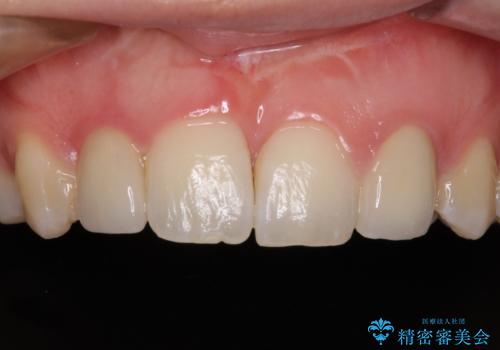

- 近医にて奥歯の抜歯が必要と言われたとのことで来院された患者様です。

診査の結果、歯が破折しており、抜歯が必要な状態でした。

最後方歯であるため、入れ歯かインプラントかどちらかの補綴治療を行うこととなりますが、ご希望によりインプラント補綴治療を行うこととしました。

インプラントにはストローマン社のSLActiveを使用し、埋入から補綴までおよそ3か月と、短期間で治療を進めることができました。